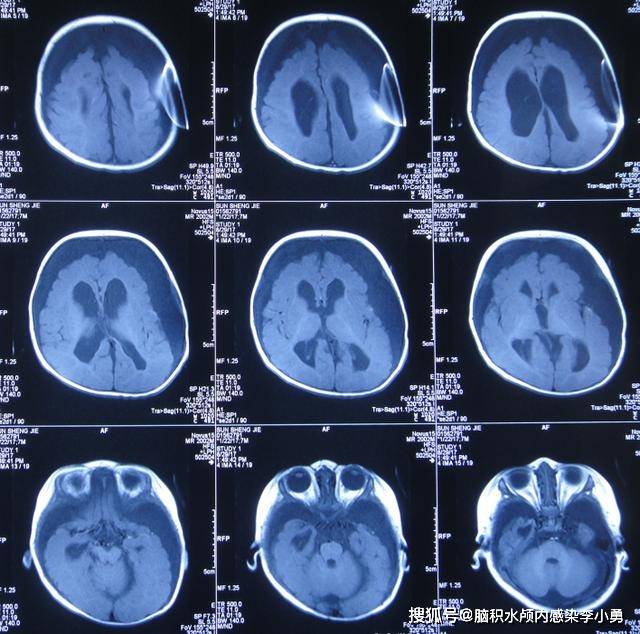

脑水肿,脑积水的分类及图像表达,一文归纳

各类型脑水肿的鉴别